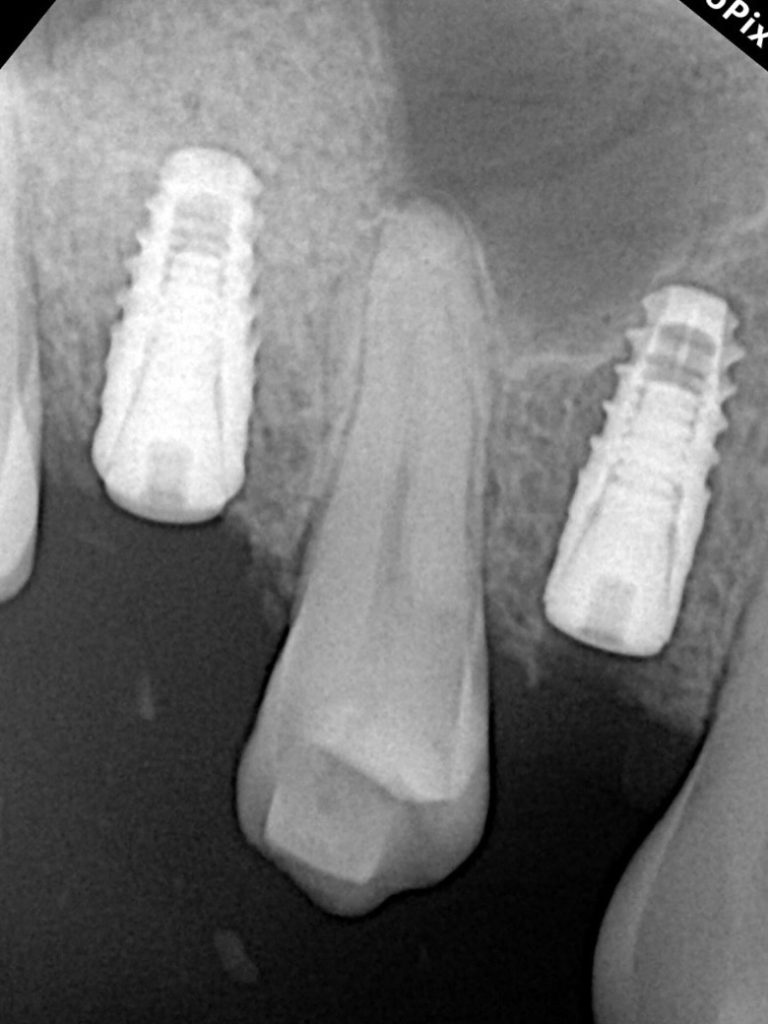

A Swiss-made tapered implant (4.1 × 10 mm) was inserted into the prepared osteotomy with 40 Ncm torque (Fig 4). The implant apex extended slightly into the augmented sinus cavity, achieving excellent primary stability and favorable bone compression.